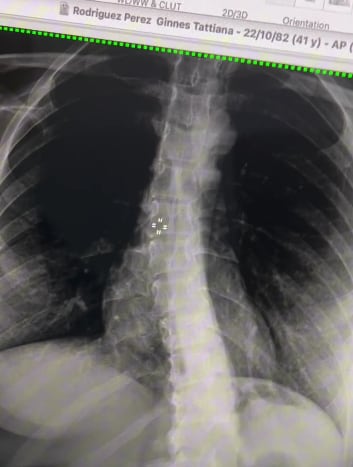

Rodríguez padece escoliosis, que es una curvatura anormal de la espina dorsal y que en su tipo más grave, puede generar trastornos serios como la parálisis cerebral o distrofia muscular, según el sitio MedlinePlus.